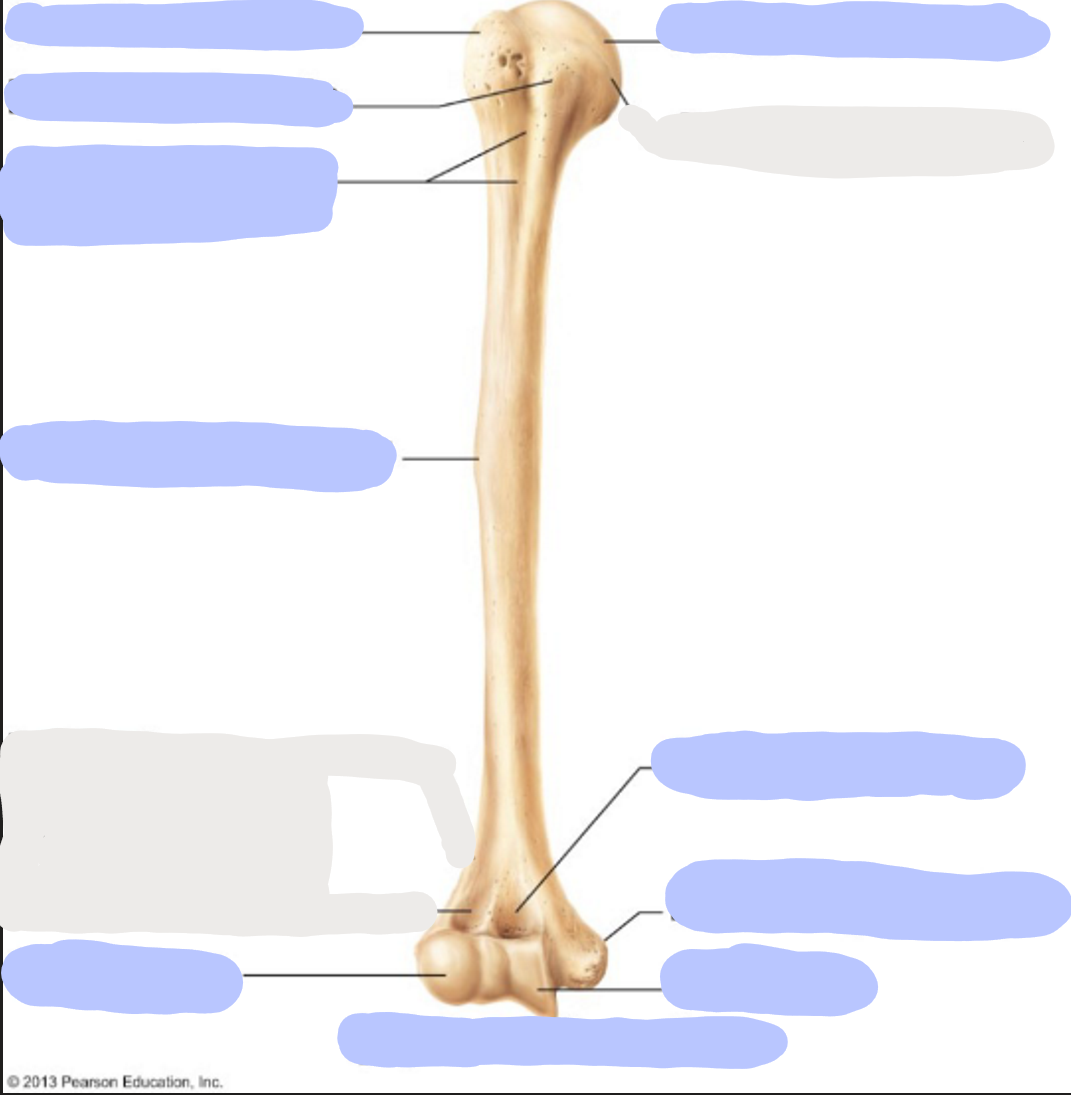

What is this picture of?

Anterior view of the right humerus

What is here?

Where is the Head of the humerus?

What is here?

Where is the Greater Tubercle of the humerus?

What is here?

Where is the Lesser Tubercle of the humerus?

What is here?

Where is the Intertubercular Sulcus of the humerus?

What is here?

Where is the Deltoid Tuberosity of the humerus?

What is here?

Where is the Capitulum of the humerus?

What is here?

Where is the Trochlea of the humerus?

What is here?

Where is the Medial Epicondyle of the humerus?

What is here?

Where is the Coronoid Fossa of the humerus?